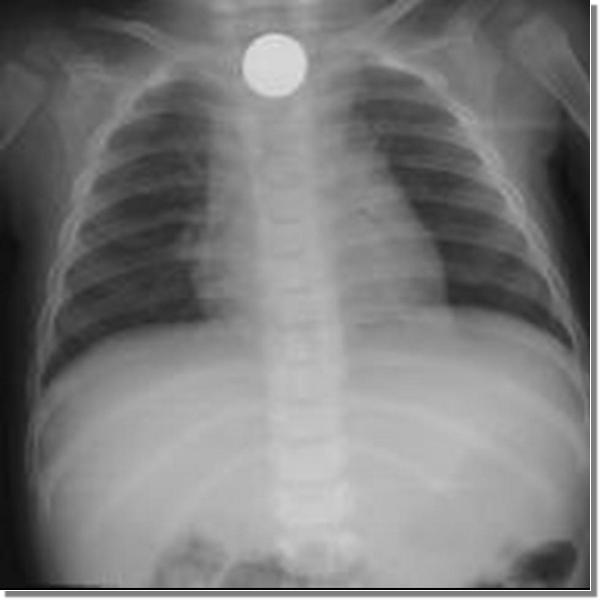

三歲女娃兒誤吞十元硬幣,經以食道鏡夾出後,順利解決危機。

如此反覆經過一段時間,小朋友雖然吐出了一大堆食物,就是不見十元硬幣,媽媽隨即把女兒送到醫院治療。經醫師檢查,發現硬幣就卡在食道裡,進而以食道鏡順利取出硬幣。只是醫師在夾出硬幣的同時,也發現病人的咽喉與食道有多處糜爛性的傷口。